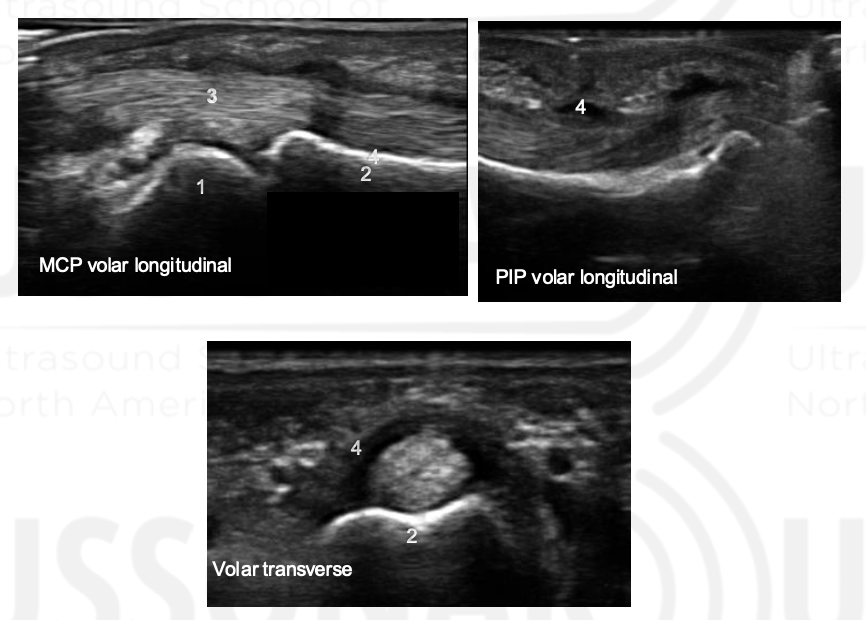

Name 1-4

Thickened A1 pulley

Tendon thickening compared to adjacent tendon. Also note tendon is thicker distal to A1 puley. On dynamic imaging, this impinged onto the A1 pulley.

MCP

Phalanx